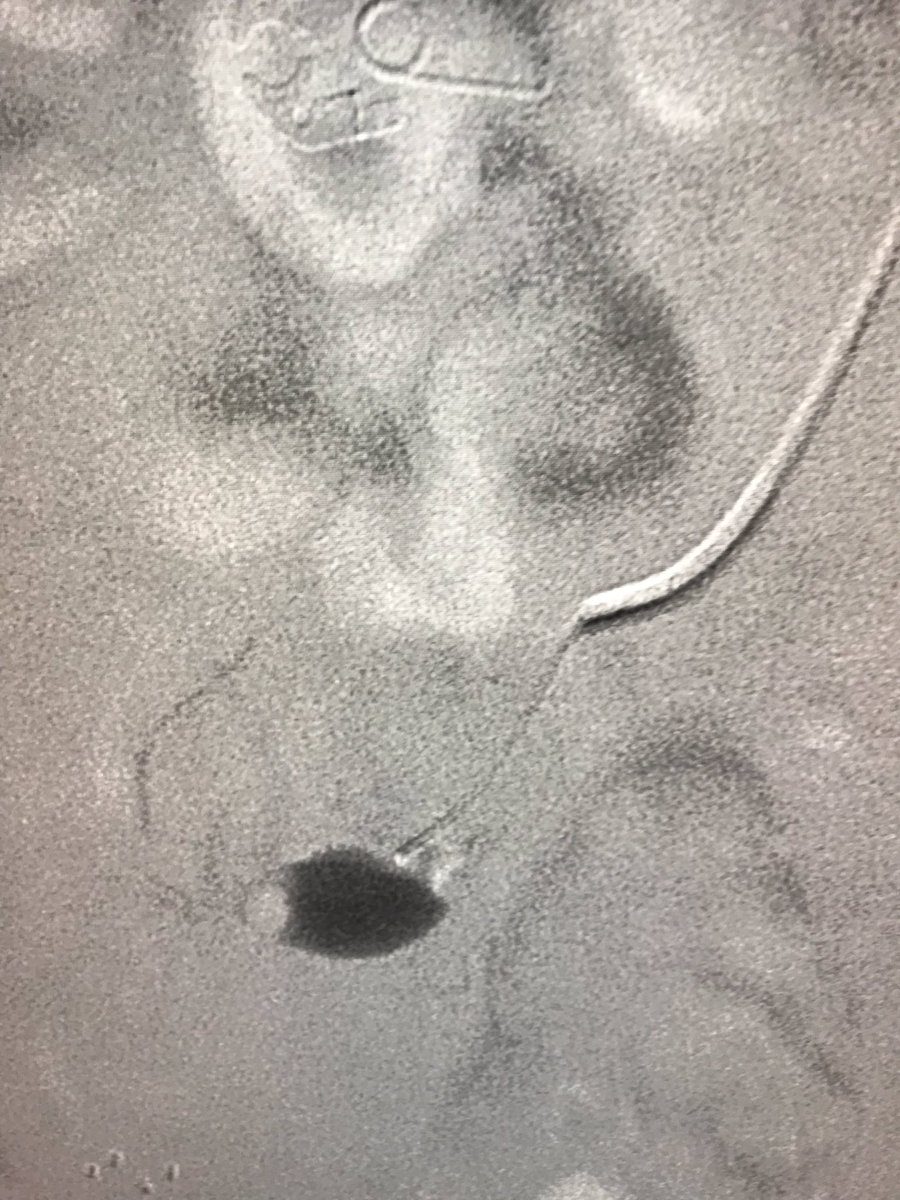

Transradial n-BCA Glue Embolization of Giant Pelvic Arteriovenous Malfor... youtu.be/BlGp9gZV6wk via @YouTube